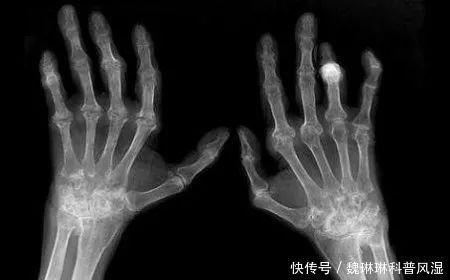

类风湿患者怕冷原因

类风湿患者为什么这么怕冷,这与多种因素有关。

患者微循环差

类风湿患者因为滑膜炎和血管炎的影响,会出现关节局部微循环障碍,尤其是手足等小关节部位。不少患者一到冬天就手脚冰凉,穿再多都热不起来。关节局部微循环差会让患者血液流通不良、营养物质和能量也不能及时被输送到应该的位置帮助机体抵御低温的天气,类风湿患者自然就会感到寒冷。